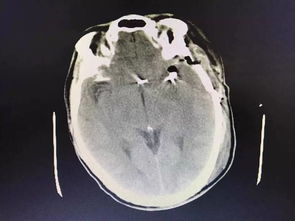

病情分析: 腦動脈血管瘤夾閉手術(shù)后偏癱失語 病情指導(dǎo): 需要繼續(xù)治療,應(yīng)該是傷及神經(jīng)了,腦血管瘤的治療:全切除腫瘤可治愈此病,但由于腦血管瘤的位置,瘤體的大小往往使瘤體不能完全切除,術(shù)中瘤結(jié)節(jié)的遺漏亦是腫瘤復(fù)發(fā)的一個因素。

中醫(yī)治療:服用單方含量16%以上的人參皂苷Rh2(護(hù)命素),三七,蟲草等具有抗腫瘤功效的藥物,特別是人參皂苷Rh2(護(hù)命素),是現(xiàn)代化中藥分子藥物,具有提高免疫力和抗腫瘤的雙重功效,是小分子結(jié)構(gòu),易透過人體血腦屏障,發(fā)揮功效,控制和抑制殘留腦部腫瘤細(xì)胞的生長。